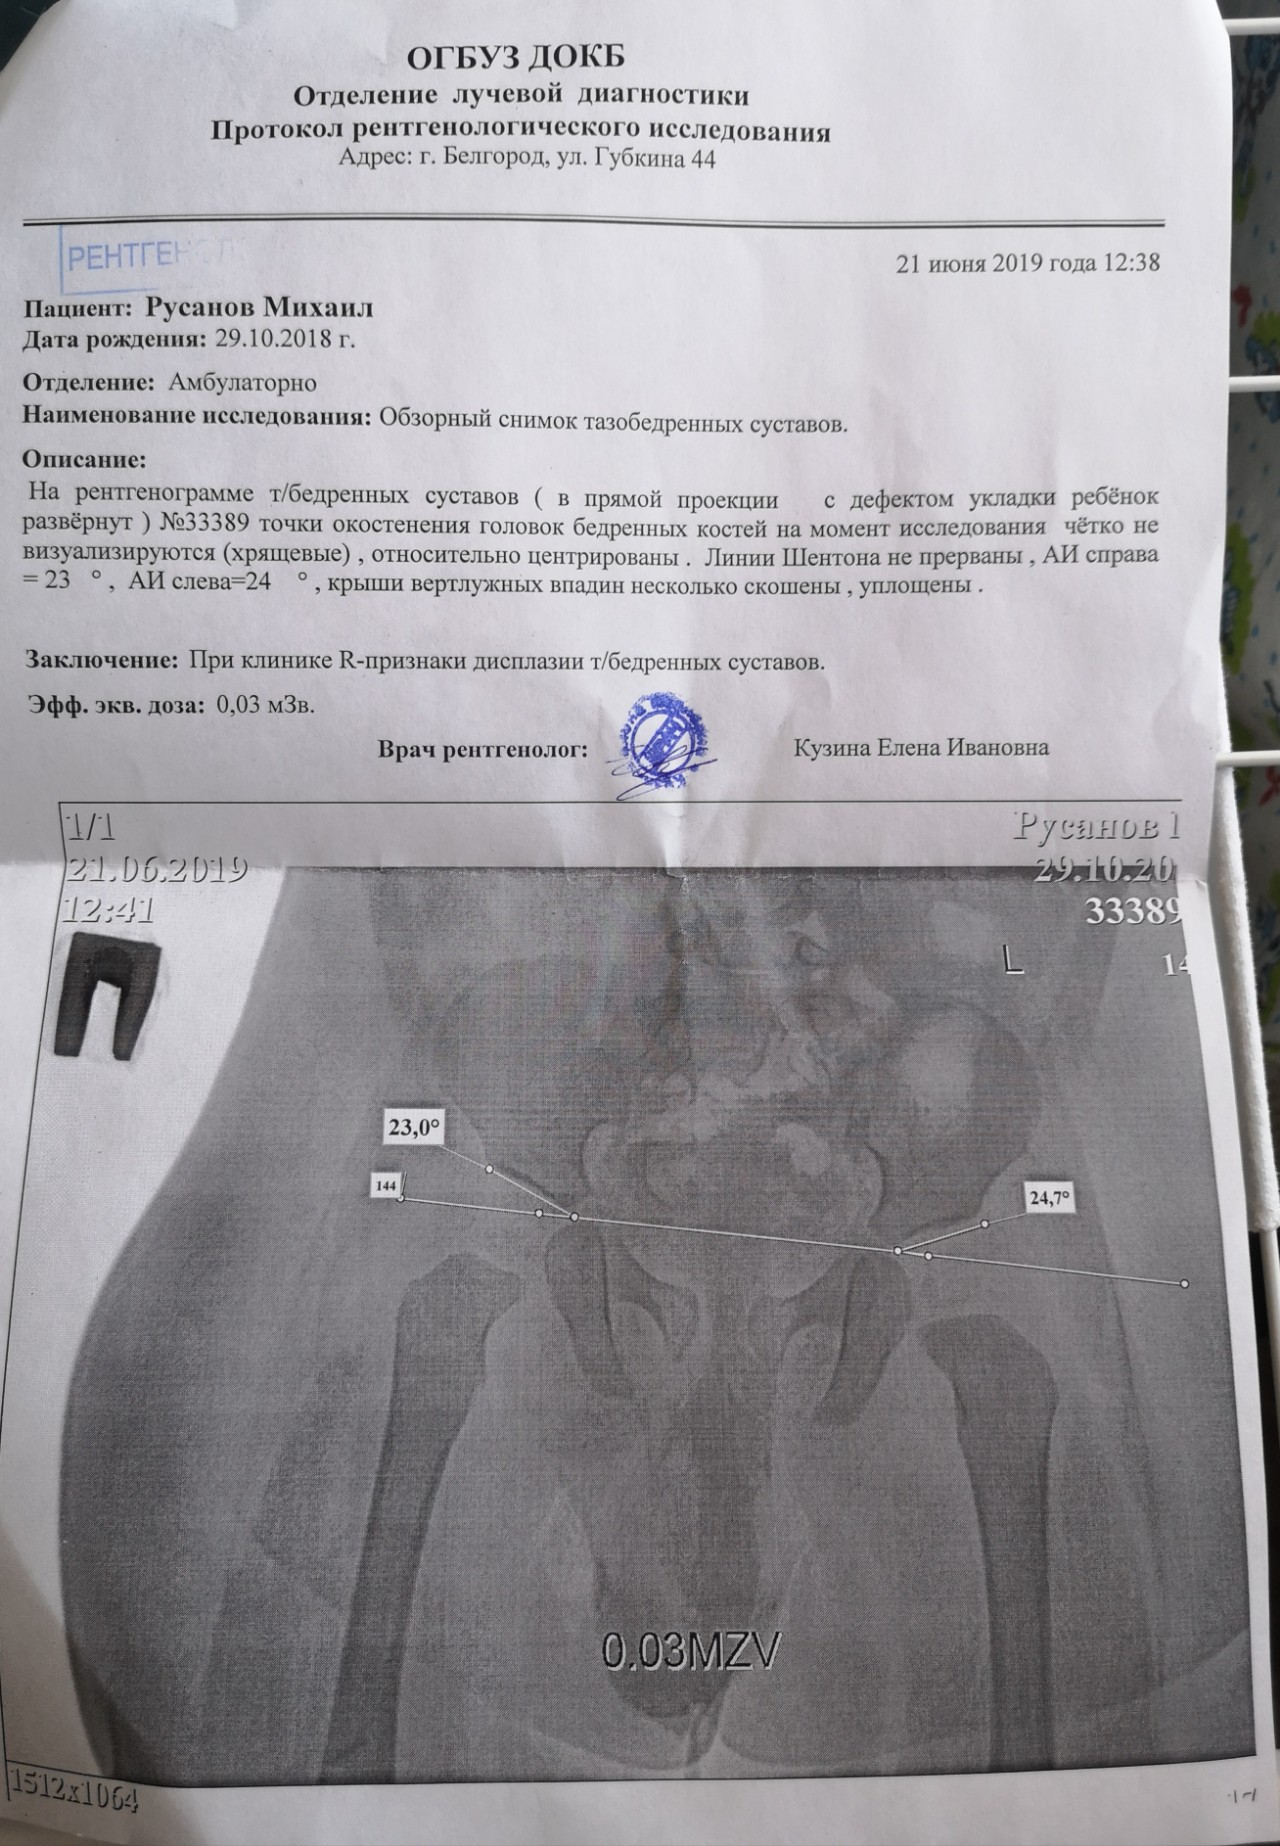

Рентген ТБС: Нормальные показатели

Раздел: Необычные решения